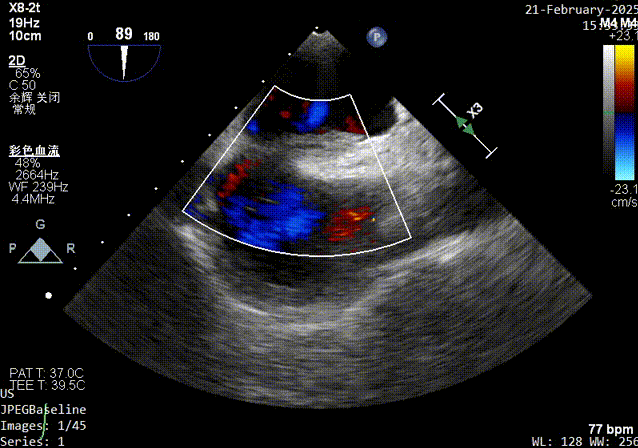

color超声影像

器械进入前TEE彩超影像

锁结操作完成后彩超影像